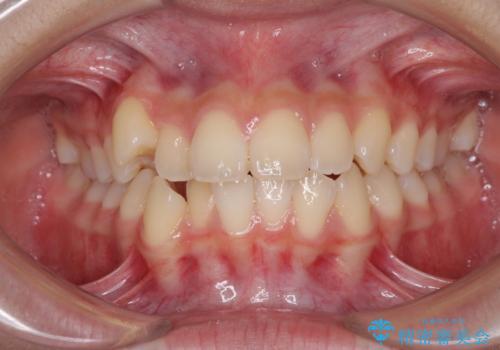

出っ歯を改善した後に真っ白な歯に 矯正歯科治療と審美歯科治療